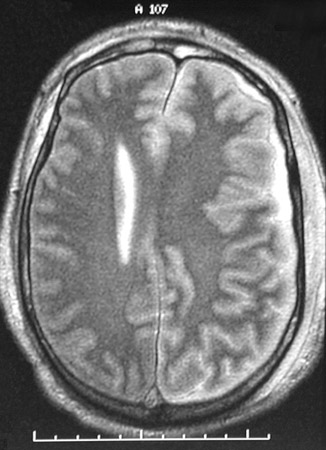

| The T2 weighted MRI scans in axial view above and below show bright fluid in the subdural region on the left, representing a subdural empyema. Note also the effacement of the left ventricle with midline shift due to the brain swelling from the inflammation. This may represent hematogenous spread of infection, or a prior subdural hematoma may become infected. Both events are not common. |